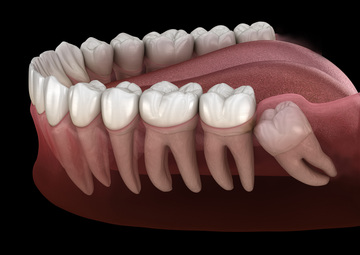

親知らず、どうしたらいいの?

親知らずが気になる…という方、意外と多いのではないでしょうか?

「奥の歯ぐきが腫れて痛い」「物が詰まりやすい」「歯ブラシが届きにくい」

そう感じたことがあるなら、親知らずが関係しているかもしれません。

親知らずは、まっすぐ生えていなかったり、半分だけ歯ぐきから出ていたりすることが多く、プラーク(歯垢)が溜まりやすい場所です。

その結果、歯ぐきが腫れたり、膿が出たり、口が開きにくくなったりといった症状が出ることがあります。

親知らずの位置や生え方によって、抜歯の難しさや痛みの感じ方は変わります。

下の親知らずや横向きに生えている場合は、歯ぐきを開いたり、歯を分割して抜くこともありますが、処置中は麻酔が効いているので痛みはほぼありません。